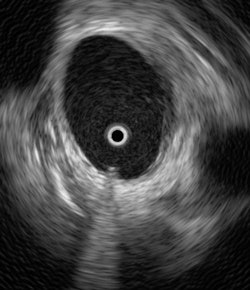

|  |

| Ultrasound catheter in the heart. The heart's inner walls appear in white, and blood is black. The catheter's metal tip reflects the ultrasound wave and produces a white circle with a white cone-shaped shadow behind it. The catheter's movement within the heart can be monitored in real-time without the need for x-ray guidance. |